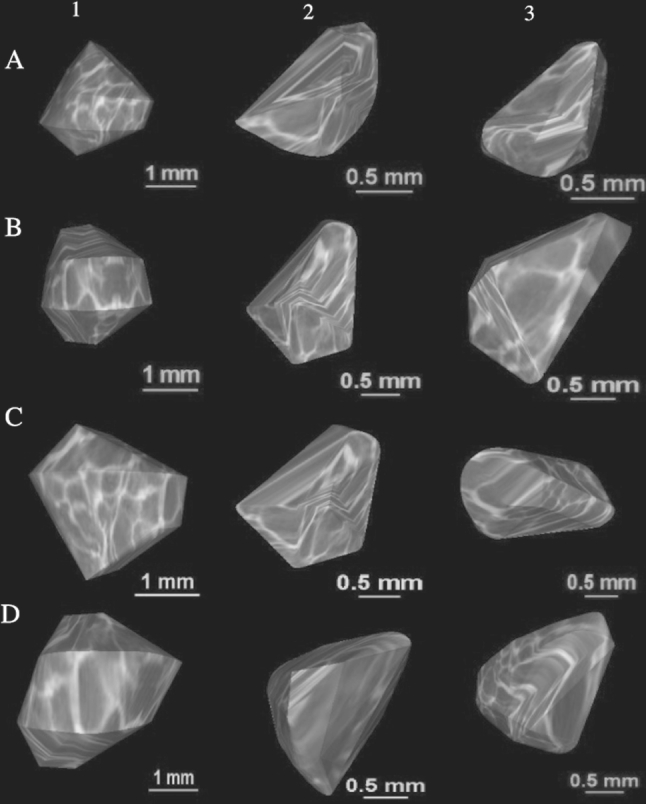

Fig. 1.

CT of a female fetus aged 25 weeks recorded in DICOM formats (a) and assessed by Osirix 3.9 in frontal (b), lateral (c), and horizontal (d) planes

The size of the ossification center of the C4 vertebral body has been presented in Table 3, while Fig. 4 presents the three ossification centers of vertebra C4 within its body (1), and right (2) and left (3) neural processes in fetuses aged 17, 22, 26, and 30 weeks, respectively. During the analyzed period, the transverse (Fig. 5a) and sagittal (Fig. 5b) diameters of the ossification center of the vertebral body grew logarithmically from 1.60 to 3.74 ± 0.44 mm, and from 1.32 to 3.37 ± 0.12 mm, according to the following models: y = − 8.836 + 3.708 × ln(Age) ± 0.334 (R 2 = 0.76) and y = − 7.748 + 3.240 × ln(Age) ± 0.237 (R 2 = 0.83), respectively. As a result, the growth dynamics for transverse and sagittal diameters decreased with gestational age, from 0.21 to 0.13 mm per week, and from 0.19 to 0.11 mm per week (P < 0.01), respectively. During the study period, the sagittal-to-transverse diameter ratio of the ossification center (Fig. 5c) increased from 0.86 ± 0.04 to 0.88 ± 0.11 (P < 0.05). The cross-sectional area of the ossification center (Fig. 5d) increased linearly from 3.70 mm2 in fetuses aged 17 weeks to 10.23 ± 3.14 mm2 in fetuses aged 30 weeks, according to the function: y = −4.690 + 0.437 × Age ± 1.172 (R 2 = 0.63). Similarly, the volumetric growth of the ossification center (Fig. 6a), from 4.67 to 13.45 ± 3.20 mm3, followed linearly as y = −5.917 + 0.582 × Age ± 1.157 (R 2 = 0.77).

Fig. 4.

Ossification centers of the vertebral body (1), and right (2) and left (3) neural processes of vertebra C4 in fetuses aged 17 weeks (a), 22 weeks (b), 26 weeks (c), and 30 weeks (d)